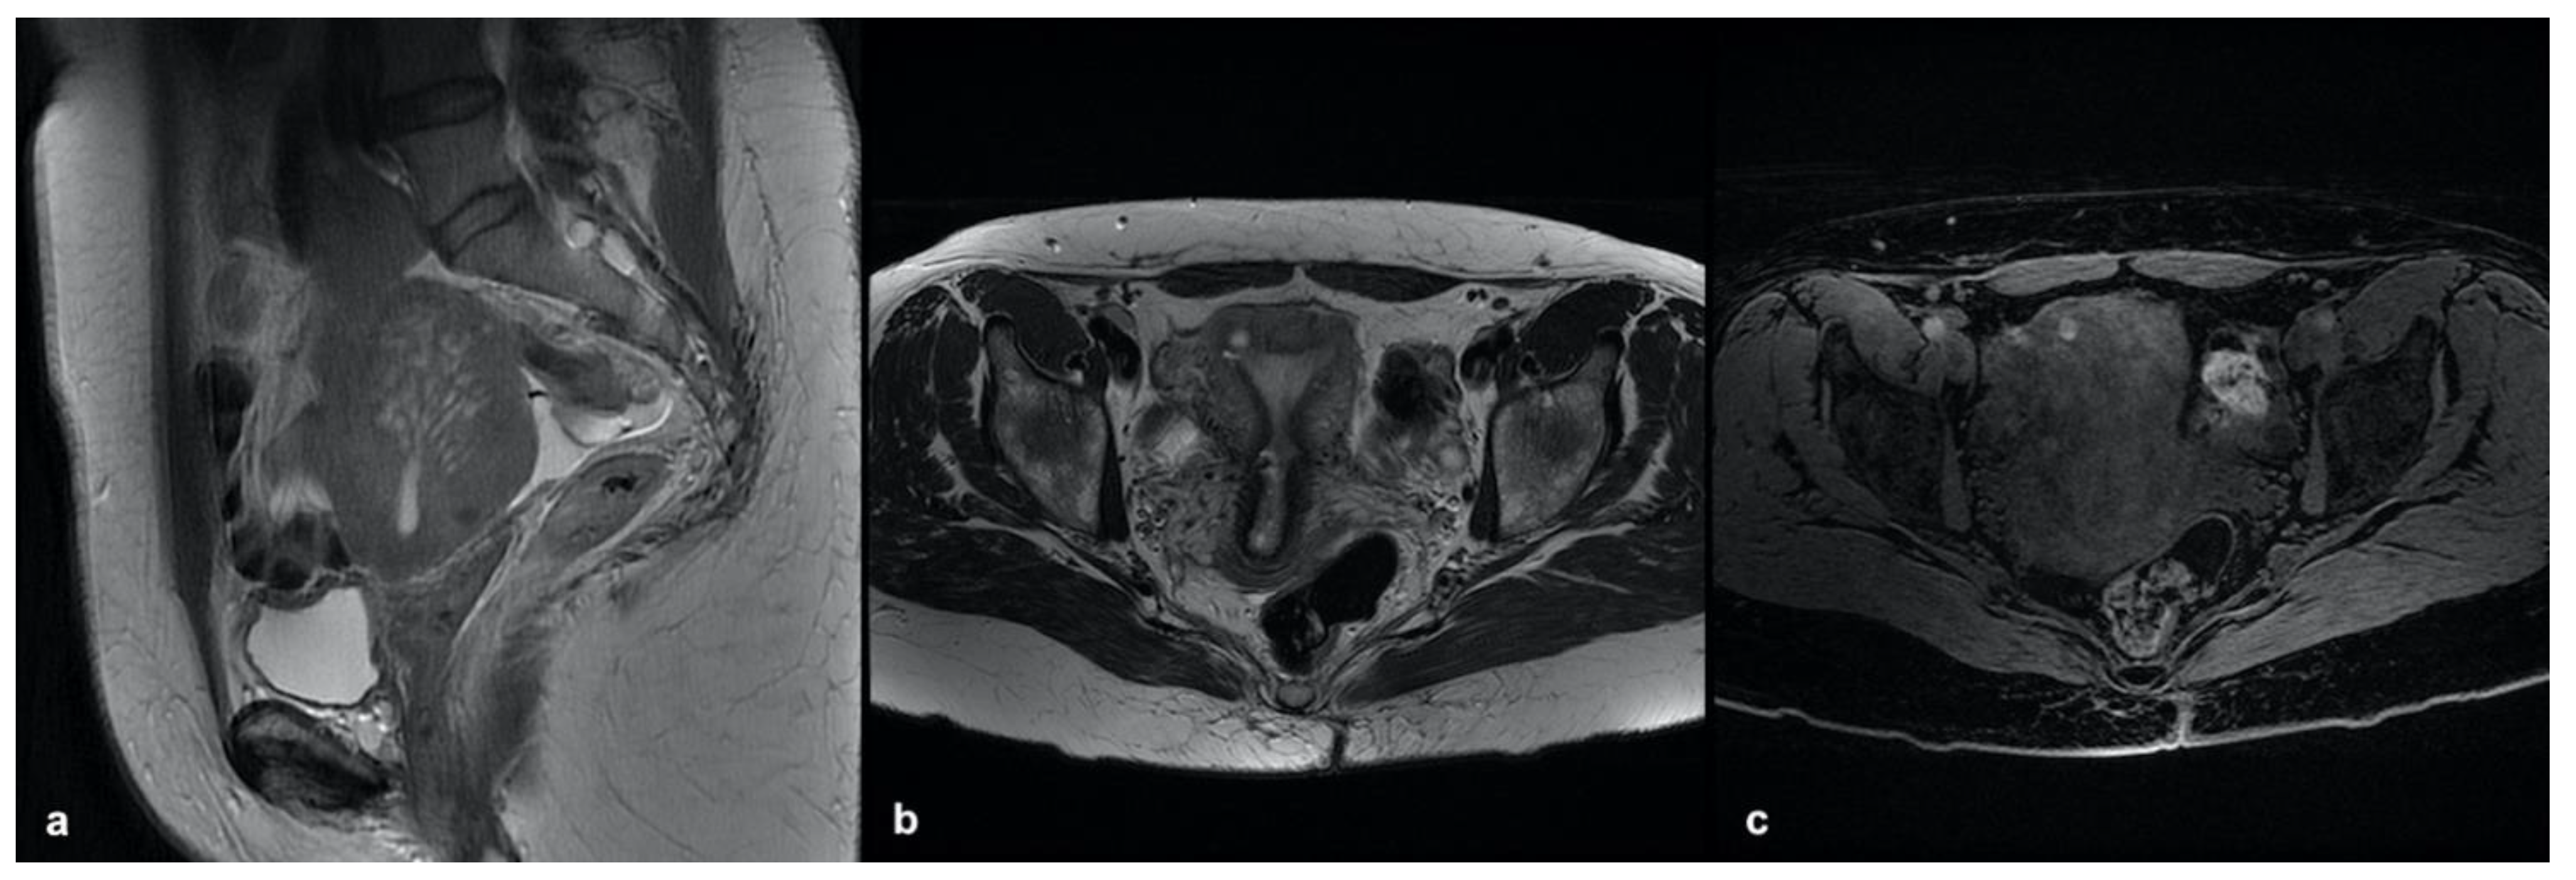

3.3.1. Internal Adenomyosis

3.3.2. External Adenomyosis

3.3.3. Adenomyoma